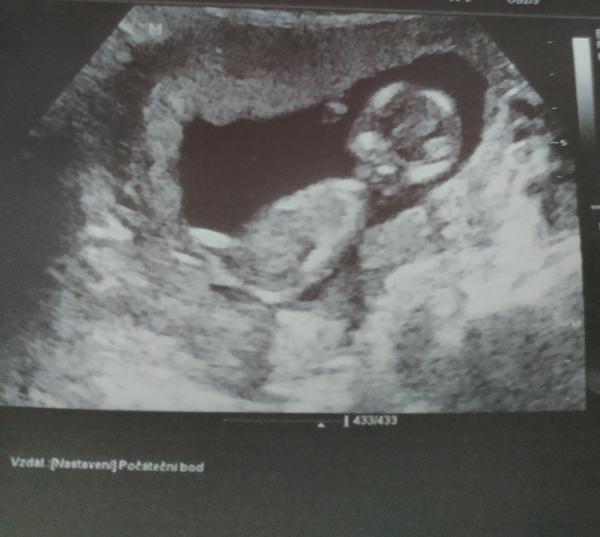

Ahojky holky, tak já už mám po screeningu. Konečně jsem viděla mrňouska, i když měl pan doktor dost velký problém nás změřit, páč tam mimčo skákalo jak na trampolíně a furt se chtělo schovávat🤣 ale na konec (asi po hodině) se povedlo a všechno je prý v pořádku 🙏🙏 pohlaví zatím nevíme, prý snad na příští kontrole 😊